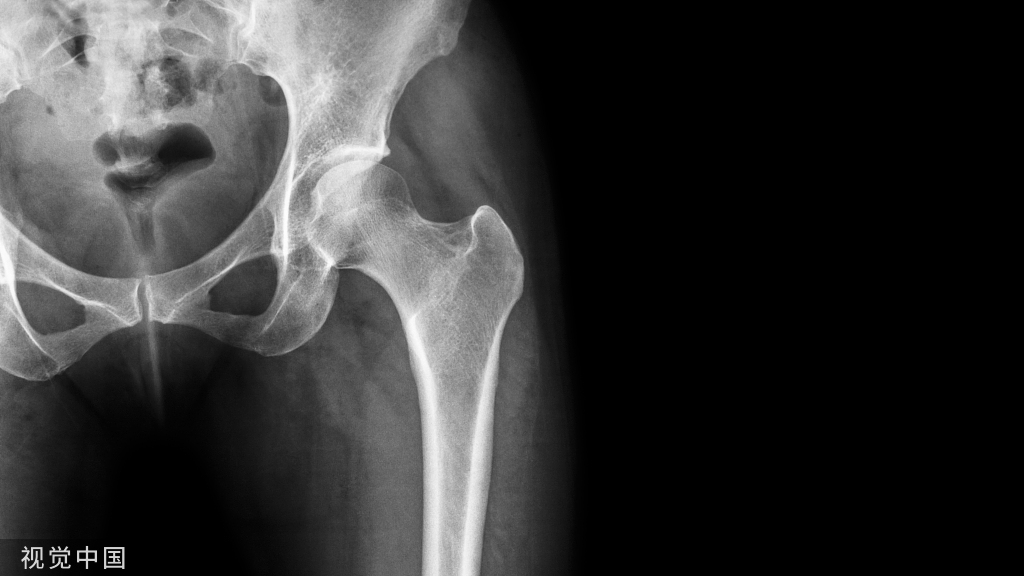

图4 胫骨近端骨折,同理将Poller钉置于锐角处。